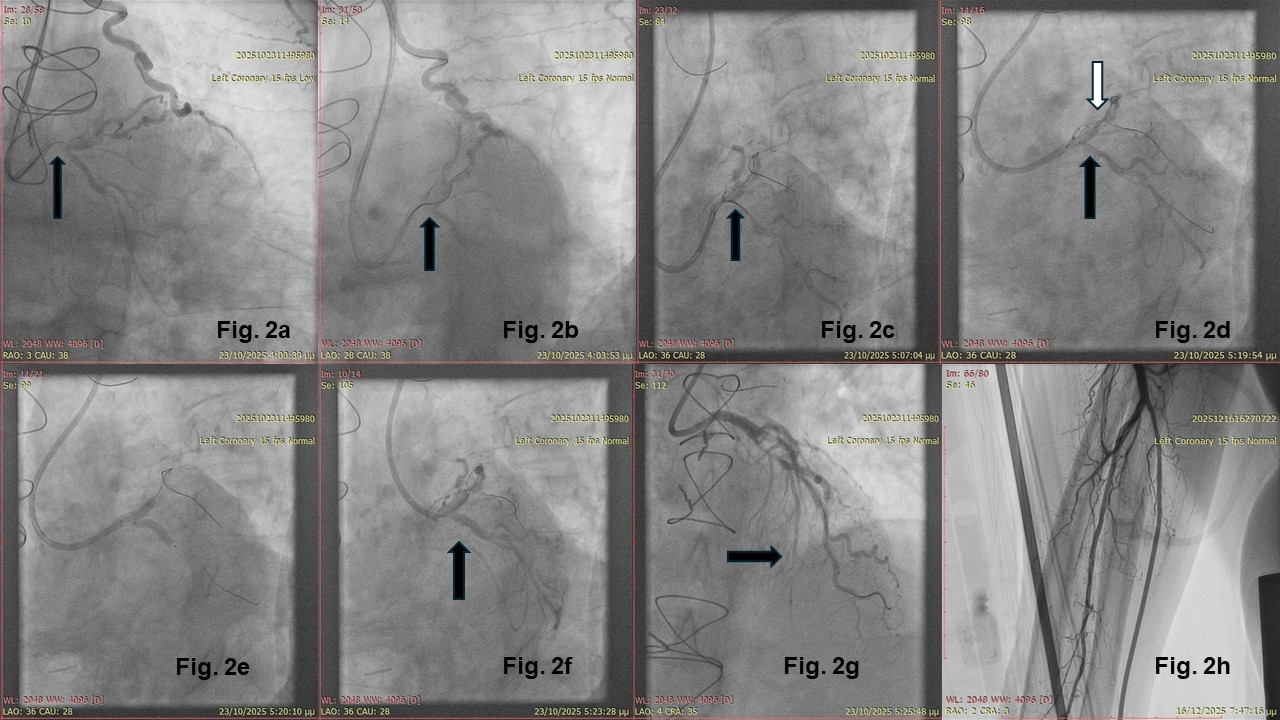

According to patient preference, we proceeded with percutaneous coronary intervention (PCI) of the left main (LM) chronic total occlusion (CTO). The CTO procedure setup included bi-ulnar access under ultrasound guidance, a 7F 3.5 CLS guiding catheter at the ostium of the LM, and a 6F IMA guiding catheter at the LIMA. Antegrade wiring escalation technique with a Gaia Second (ASAHI INTECC) (Figure 2A) and a Turnpike Spiral microcatheter (Teleflex) support was successful, with the antegrade wire advancing through the proximal LAD to the major diagonal branch (Figure 2B). The Gaia Second guidewire was then exchanged for a workhorse wire.

After predilation of the LM and proximal LAD, multiple attempts were made to wire the left circumflex artery (LCX) using a dual microcatheter system (ReCross [IMDS] initially, followed by a SASUKE [ASAHI INTECC]) (Figure 2C). A 2-stent technique, the reverse T-stenting and small protrusion (TAP) technique, was then employed. In this technique, a stent is first inflated at the side branch (here, the LCX) while simultaneously inflating a 1:1 noncompliant balloon at the major branch. Minimal stent strut protrusion does not require rewiring (Figure 2D and E). A second stent is then placed from the LM to the LAD (Figure 2F). Rewiring, kissing balloon inflation, and the proximal optimization technique follow, completing the LM stenting (Video 2).

Incomplete filling of the distal LAD was observed, which appeared to be partially occluded more distally (Figure 2G). The ulnar artery remained patent after PCI, as shown by forearm angiography (Figure 2H). The procedure was intentionally stopped after balloon dilation of the proximal part of the LAD and the diagonal and scheduled for completion after 4 to 8 weeks. This staged approach, called the investment CTO strategy, has been shown to be safe and more effective than the standard 1-stage CTO procedure in difficult CTO cases.